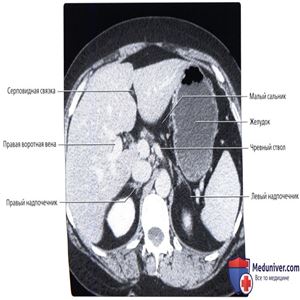

КТ с контрастированием: нормальное взаиморасположение желудка и прилегающих органов. Обратите внимание, что желудок может быть сдавлен увеличенной печенью или селезенкой.

Обратите внимание на малый сальник, содержащий жировую ткань, сосуды и лимфатические узлы желудка и печени.

Верхняя стенка желудка прилежит к поджелудочной железе, между ними расположен только малый сальник. Желчный пузырь прилежит к антральному отделу желудка и луковице двенадцатиперстной кишки. Большая кривизна желудка касается селезеночного изгиба толстой кишки.

Антральный отдел желудка прилежит к головке поджелудочной железы кзади и желчному пузырю сбоку.